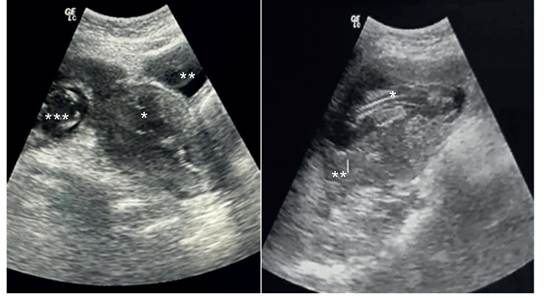

Una paciente mujer de 24 años con fórmula obstétrica G2 P2002 ingresó a emergencia obstétrica del Hospital Regional de Ayacucho, Ayacucho, Perú con el diagnóstico de aborto frustro de 14 semanas de gestación, manifestando sangrado vaginal y dolor abdominal. Tras cinco días de evolución estacionaria y ausencia de respuesta a la inducción con misoprostol y técnicas mecánicas de dilatación cervical (método de Krause), se procedió a reevaluar el caso y solicitar una nueva ecografía obstétrica, que reveló un útero vacuo y un feto fuera de la cavidad uterina, compatible con embarazo ectópico abdominal y presencia de líquido libre en la cavidad abdominopélvica (figuras 1A, 1B). Ante la sospecha de hemoperitoneo y probable embarazo ectópico abdominal, se optó por un enfoque quirúrgico. Los estudios de laboratorio indicaron hemoglobina 9 g/dL, grupo sanguíneo O Rh+, plaquetas 274,000/mL, glucosa 98, urea 19.1 mg/dL y creatinina 0,81 mg/dL.

Figura 1 a. ecografía obstétrica que muestra útero vacuo (*) junto a la vejiga (**) y cráneo del feto (***). b. feto (*) y placenta (**) sin miometrio circundante.

La ecografía desempeña un papel esencial en el proceso diagnóstico, revelando signos como la identificación de un útero vacuo contiguo a la vejiga, la ubicación del feto fuera del útero en proximidad a la pared abdominal materna, la falta de pared miometrial alrededor del feto, posturas fetales anómalas y una definición deficiente de la localización placentaria7)(8)(9, tal como se evidenció en el presente caso.